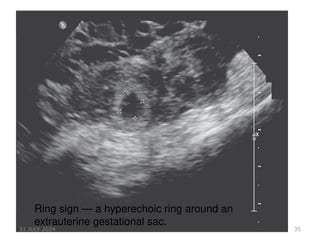

USG PICTURE

1.‘Bagel’ sign – Hyperechoic ring around gestational sac in adnexal

region

Ring sign — a hyperechoic ring around an

extrauterine gestational sac.